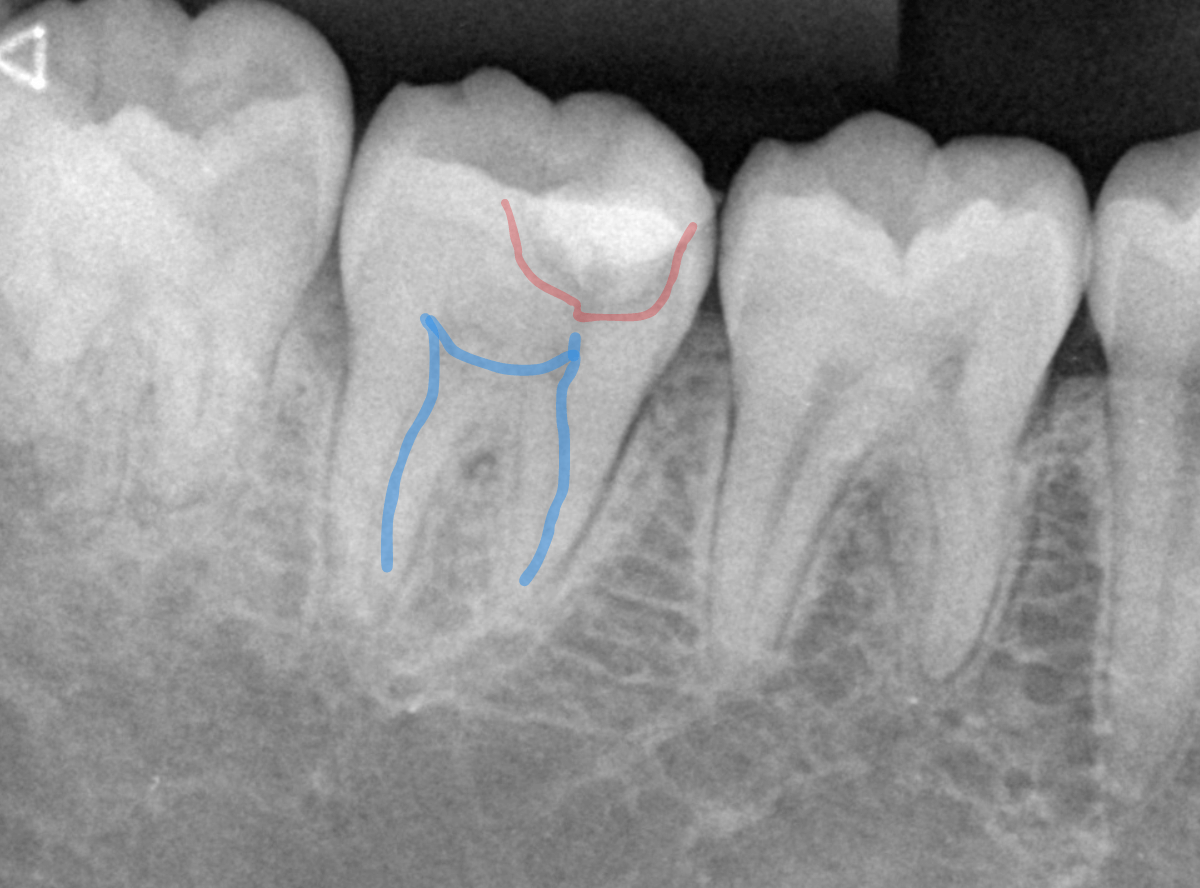

レントゲン写真で確認します。

やはり、奥歯の端が大きな虫歯になっています。

青いラインが歯の神経、赤いラインが虫歯です。

レントゲン写真上では虫歯が神経まで達しているように見えます。

これは、神経を取らないとダメかもしれません。